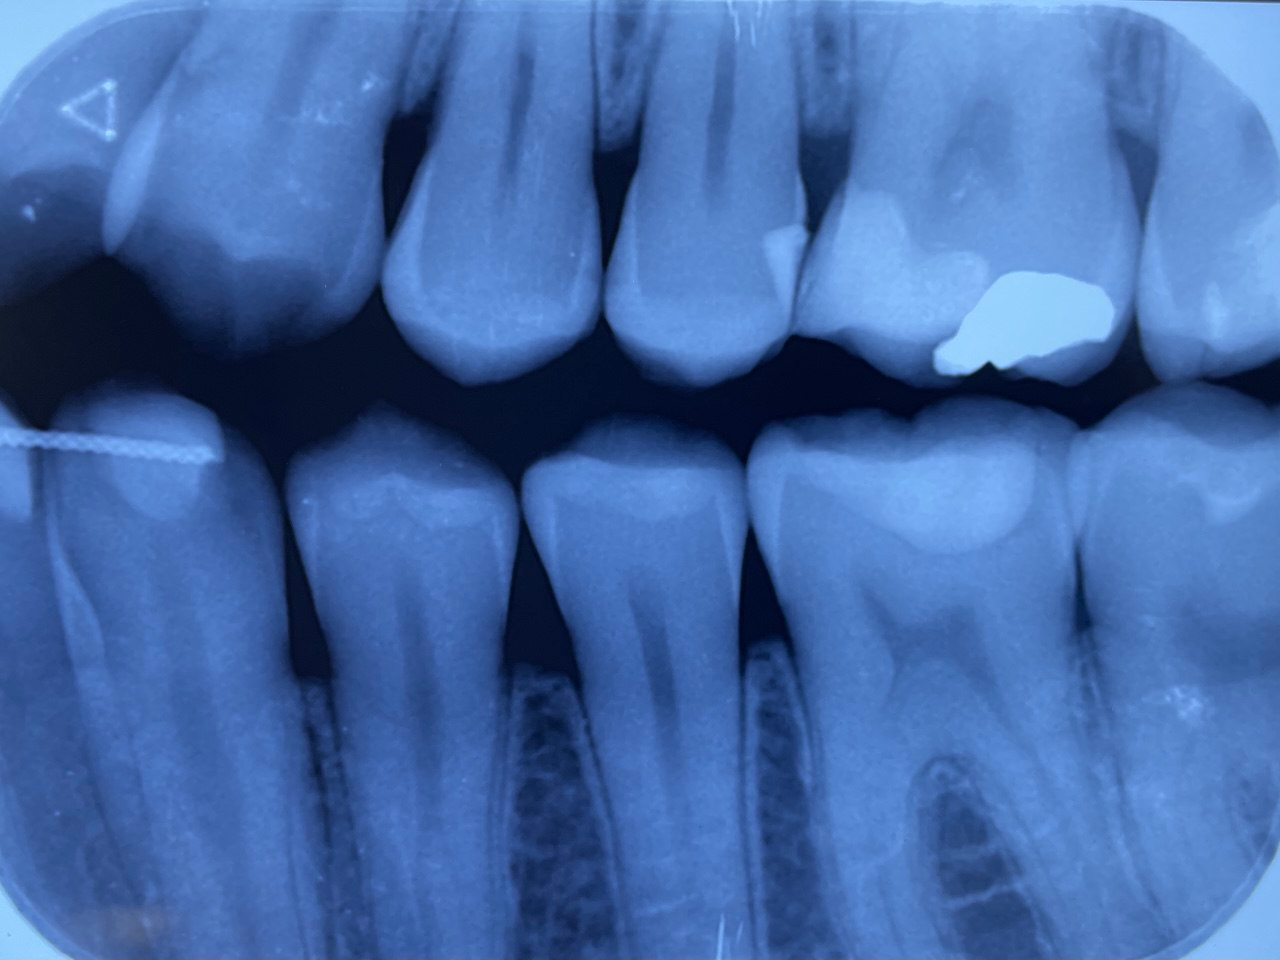

1. Which surfaces shows dental caries?

2. Which surface needs restoration?

3. What is the caries level on the distal surface of the tooth # 3.6?

4. Which surface needs restoration?

5. Which surface needs restoration?

6: What is the caries level of mesial of the tooth # 3.6?

7: What is the caries level of Distal of the tooth # 3.6?

8. Which surface needs restoration?